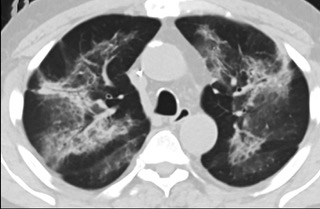

6天后的轴向CT平扫图像显示毛玻璃影变为实变和轻度结构扭曲。(同一病人CT影像)

16位被文献报道为电子烟肺炎的患者被专家判定为“病毒性感染”,即有可能是新冠肺炎的“疑诊患者”,其中更有5位临床症状和治疗情况相对完整的患者被判定为“中度可疑”。因此在2019年美国报道的电子烟肺炎中存在病毒性感染的病例,而且不排除美国电子烟肺炎中存在新冠肺炎的可能性。